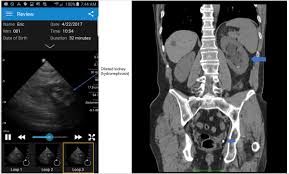

Kidney Stones Scanning Name. They originate in your kidneys but can be found at any point in your urinary tract. This imaging technique is also helpful when it comes to diagnosing cystine crystals.

The reason is that kidney stones are bright white on ct images.

The pain can be excruciating. The reason is that kidney stones are bright white on ct images. The benefits of utilizing a computed tomography ct scan for kidney stones are numerous. Calcium oxalate uric acid struvite and cystine.